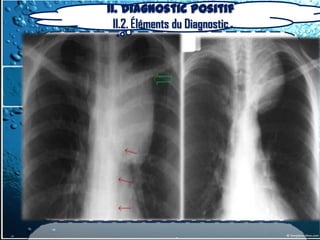

II. Diagnostic positif

II.2. Éléments du Diagnostic

a) radiographie du thorax

La “masse”= aspect d’une opacité de forme, de dimension

et de siège très variable dans médiastin

On précisera

- le type : unique ou multiple, rond,

bossé ou polycyclique

- le siège: compartiment du médiastin

- l’homogénéité ou l’hétérogénéité de

l’opacité.(calcifications)

2-2-Examen Paraclinique – Noninvasifs

2.2.1.1. Imagerie thoracique

Opacité médiastinale

- homogène

- limite externe nette

- continue,

- convexe vers le poumon,

- se raccordant en pente douce

- avec le médiastin

- à limite interne

- Invisible(noyée ds le médiastin)